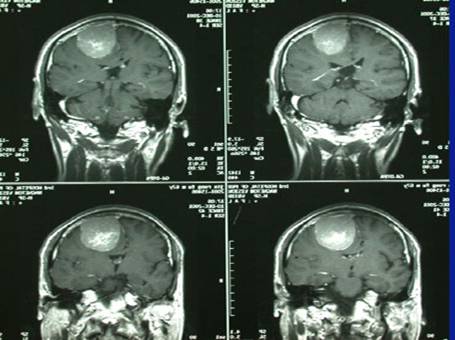

病例1-颅内巨大脑膜瘤

女性,65岁,因右半身轻偏瘫1个月入院。查MRI示:左顶叶窦镰旁脑膜瘤。如下:

术前照片